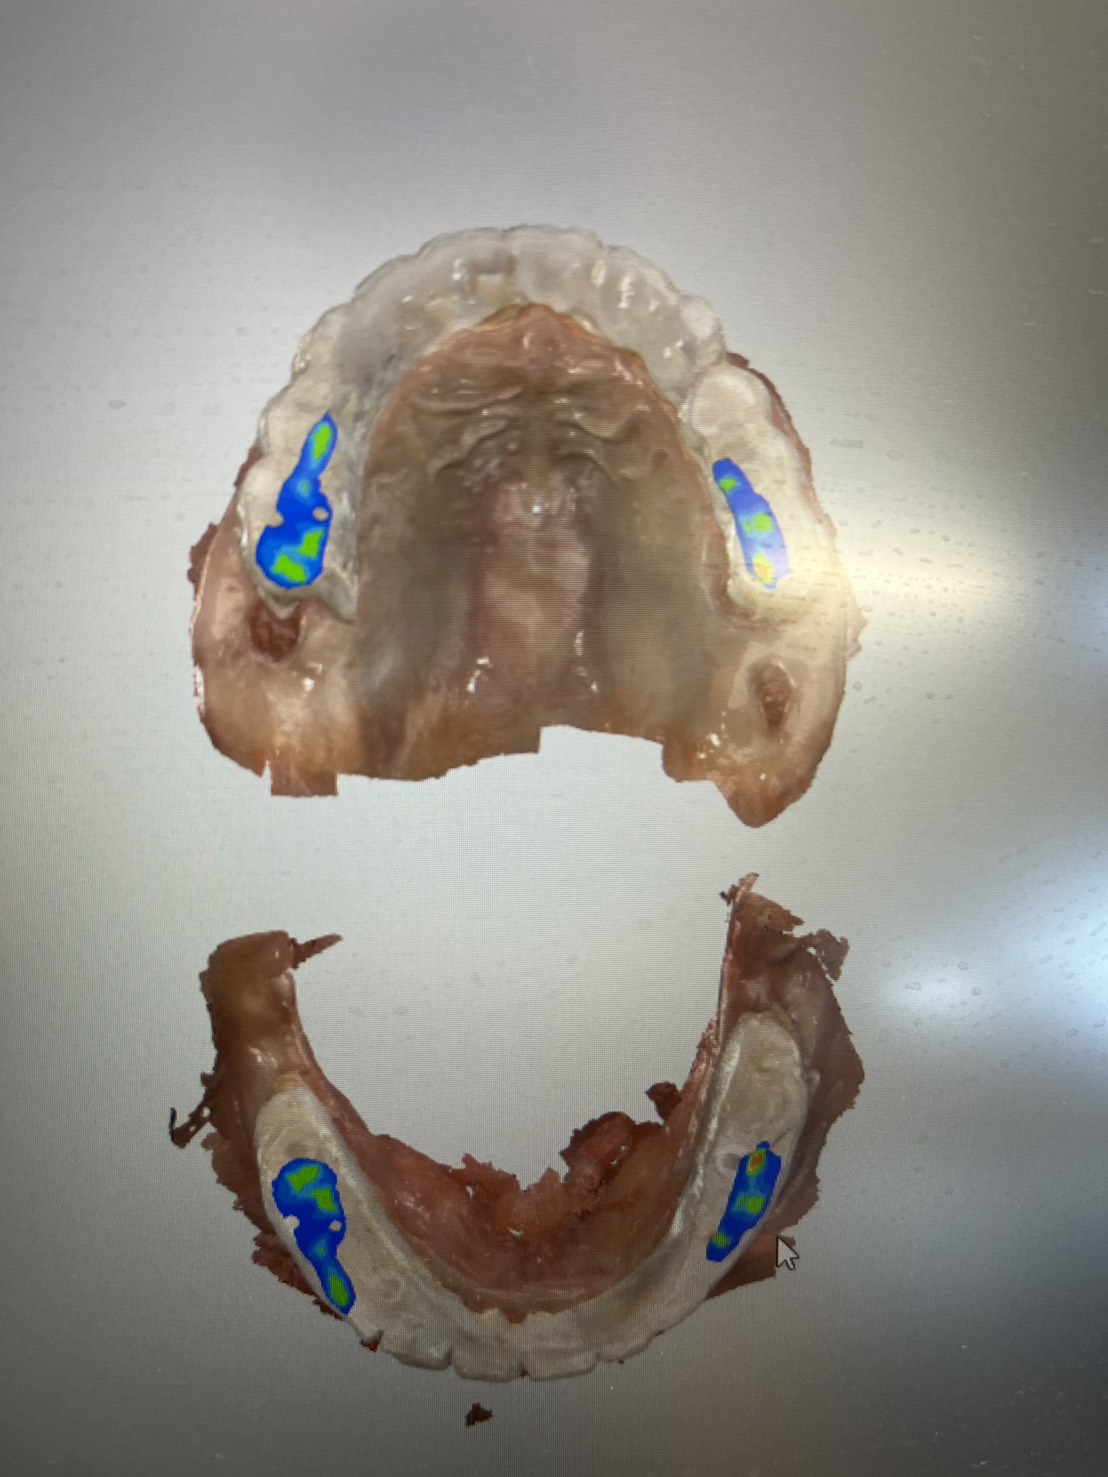

手術當天完成全口掃描,四個月後更換為最終固定假牙。這段期間,患者維持良好的生活品質,醫師也能安心照護,不用每天提心吊膽、接不完病患來電。

不需要全身麻醉,或者是舒眠麻醉的情況之下,就完成與自然牙排列相仿全口重建。不用擔心歪斜長長的植體打到顴骨或眼睛。

精奈創:最安全、最有效率的植牙技術,醫師患者都很安心。